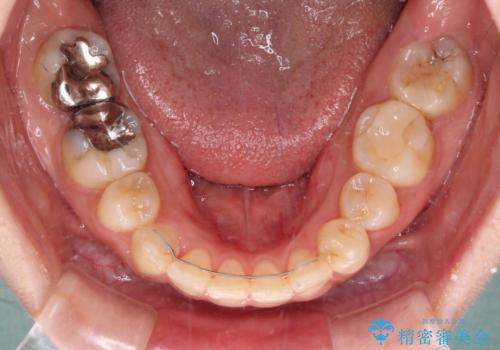

これほど顕著に裏側に隠れいてる歯ですと、仕上がったときに両隣の歯と軸に差が認められることが多いのですが、殆ど違和感のない歯並びを達成することができました。

- 矯正治療後の保定が不十分だと後戻り(元の位置に戻ろうとする動き)をします